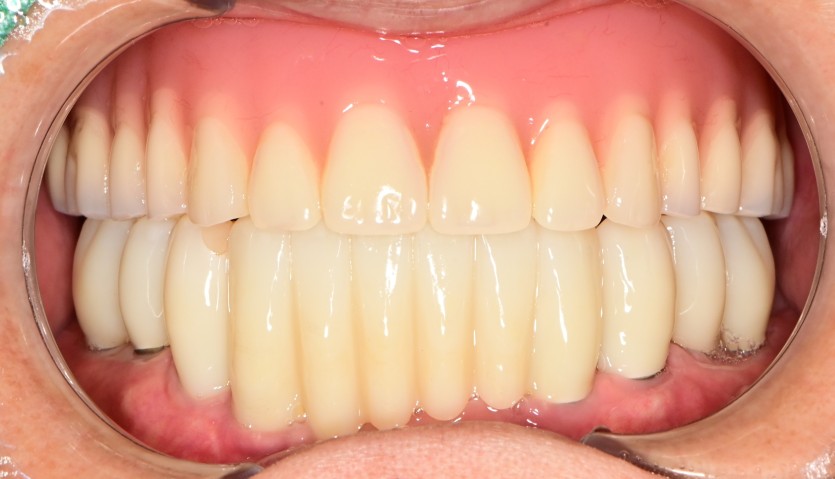

만 68세 하악 전체 임플란트 증례

하악 전체 임플란트 증례입니다.

6개의 임플란트로 완성하였습니다.